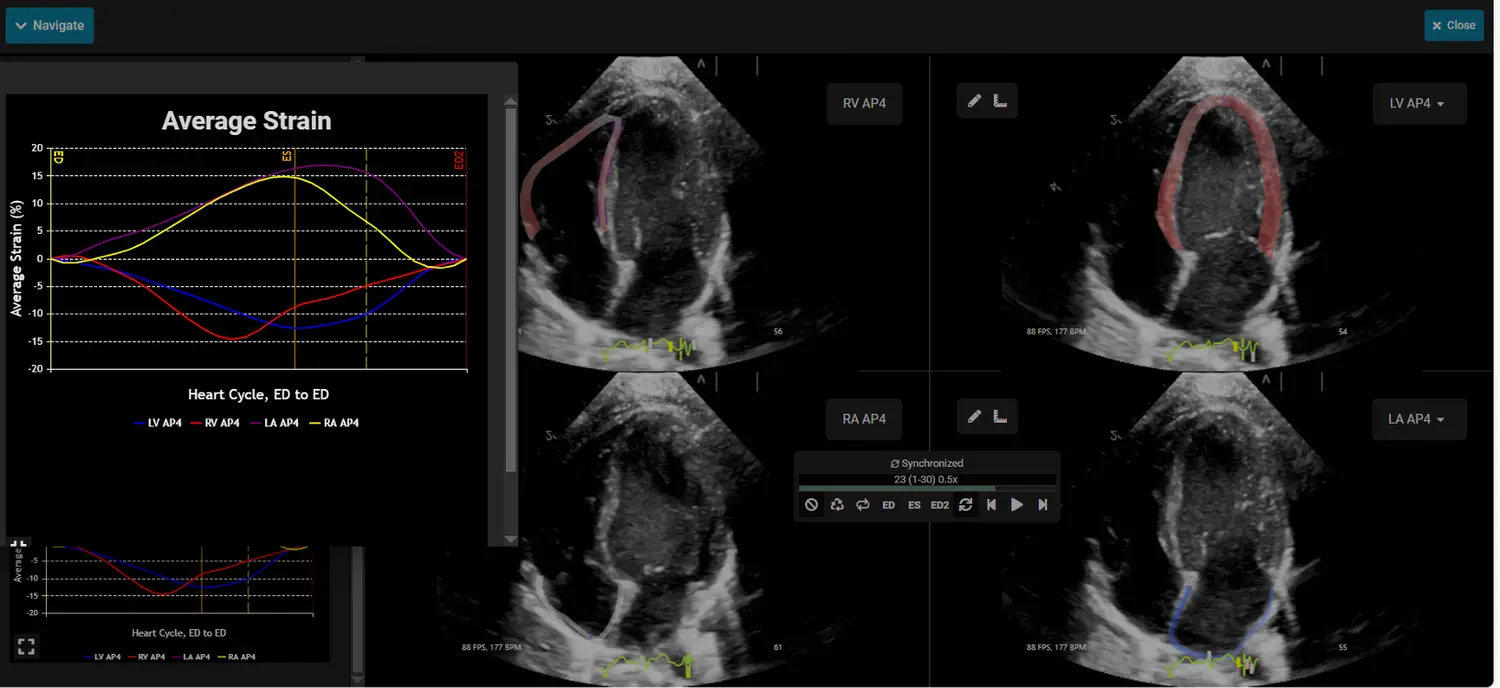

EchoInsight® Zero Footprint with AutoAssist™ is an offline, vendor-neutral, zero-footprint, zero-click echo analysis platform that runs from a single server.

Leverage EchoInsight® ZF to integrate advanced echo analysis into your routine practice.